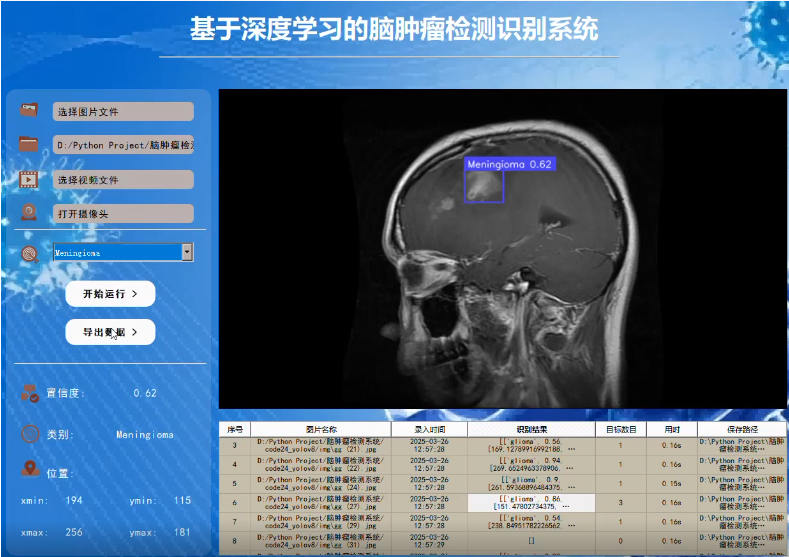

基于YOLOv8的脑肿瘤检测识别系统

5. GUI设计与推理逻辑

使用PyQt5设计GUI,并集成YOLOv8进行推理:

self.setWindowTitle("脑肿瘤检测识别系统")

self.class_names = ['glioma', 'meningioma', 'pituitary', 'acoustic']

self.btn_image = QPushButton("选择图片", self)

self.btn_video = QPushButton("选择视频", self)

self.btn_camera = QPushButton("打开摄像头", self)

self.btn_export = QPushButton("导出结果", self)

self.combo_classes = QComboBox(self)

7. 结论

以上代码提供了一个完整的框架,用于构建基于YOLOv8的脑肿瘤检测系统,包括数据处理、模型训练、GUI设计等。根据实际需求,同学;需要调整一些细节,如优化模型参数、增强数据预处理步骤等。